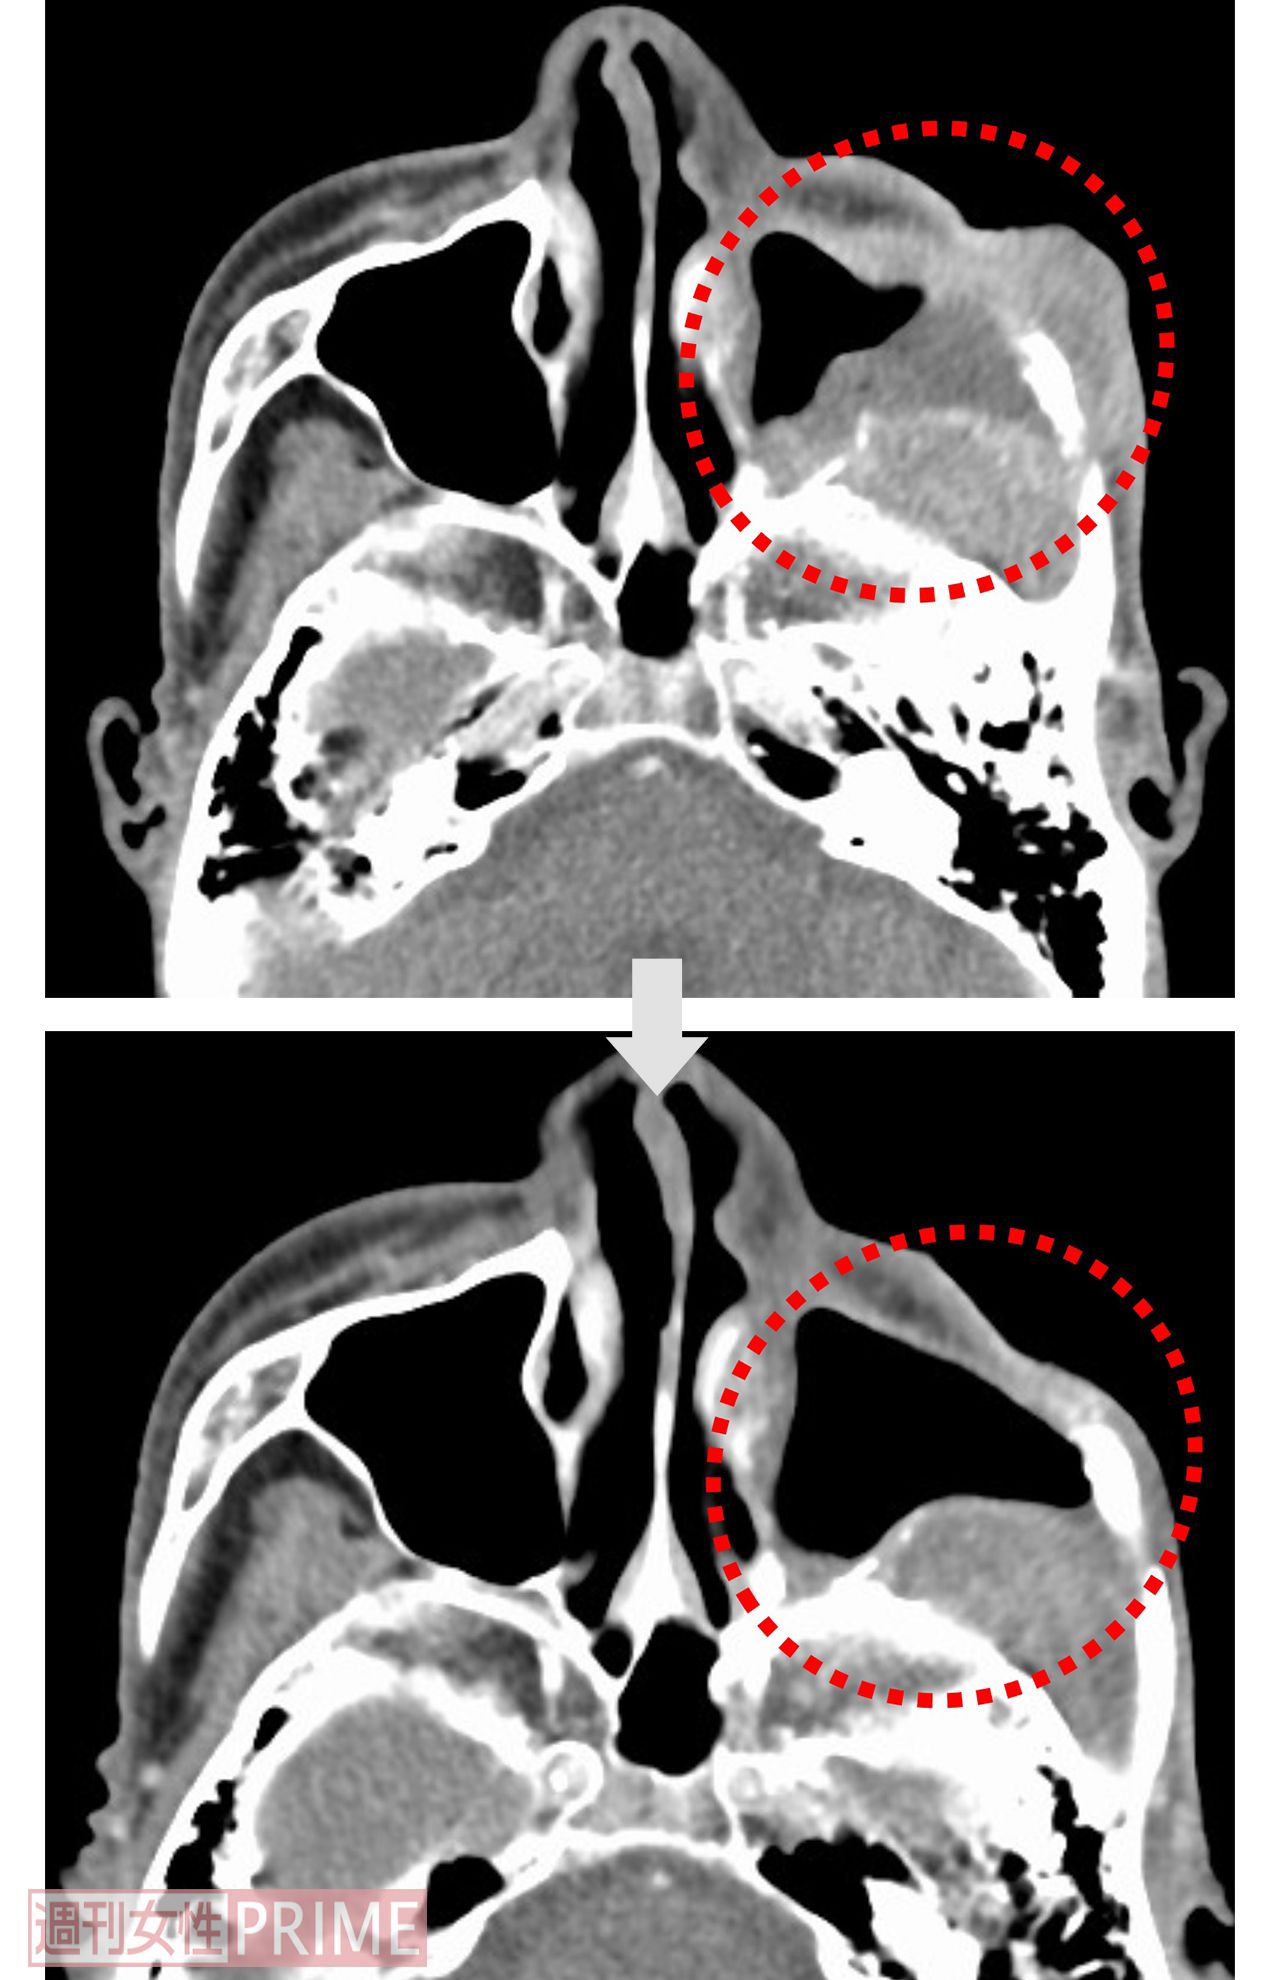

【症例1:70代男性 左上顎洞がん】BNCT治療前後のCT画像

[写真 7/10枚目] 【症例1:70代男性 左上顎洞がん】BNCT治療前後のCT画像